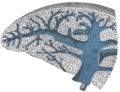

المنطقة | التكوين | الوظيفة |

red pulp | * "sinuses" (or "sinusoids") which are filled with blood * "splenic cords" of reticular fibers * "marginal zone" bordering on white pulp |

Mechanical filtration. Removes unwanted materials from the blood, including senescent red blood cells. |

white pulp | Composed of nodules, called Malpighian corpuscles. These are composed of: * "lymphoid follicles" (or "follicles"), rich in B-lymphocytes * "periarteriolar lymphoid sheaths" (PALS), rich in T-lymphocytes |

Helps fight infections. |